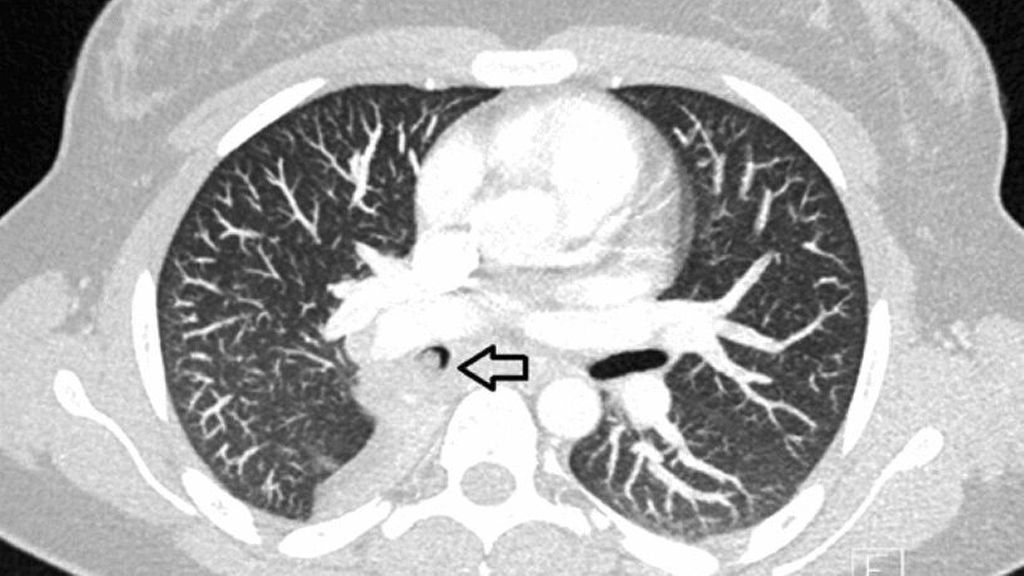

Bei der aktuellen Vorstellung wurde eine intravenöse antibiotische Behandlung initiiert, daraufhin sistierten die Hämoptysen. Thoraxsonografisch zeigte sich aber eine Persistenz der Unterlappenatelektase. In der daraufhin durchgeführten CT-Thoraxaufnahme ergab sich der Verdacht auf einen Komplettverschluss des distalen Anteils des rechten Bronchus intermedius (Abb. 2). Zur weiteren Abklärung des Befunds wurde eine flexible Bronchoskopie durchgeführt, hier zeigte sich der Befund einer endobronchialen Raumforderung (Abb. 3) mit Komplettverlegung des Bronchus, zudem waren in der endobronchialen Ultraschalluntersuchung (EBUS) suspekte Lymphknoten zu erkennen. In der gleichen Sitzung wurden aus Tumor und Lymphknoten Biopsien entnommen.

Abb. 3: Flexible Bronchoskopie, rechtsseitig, dendistalen Bronchus intermedius verlegender Tumor